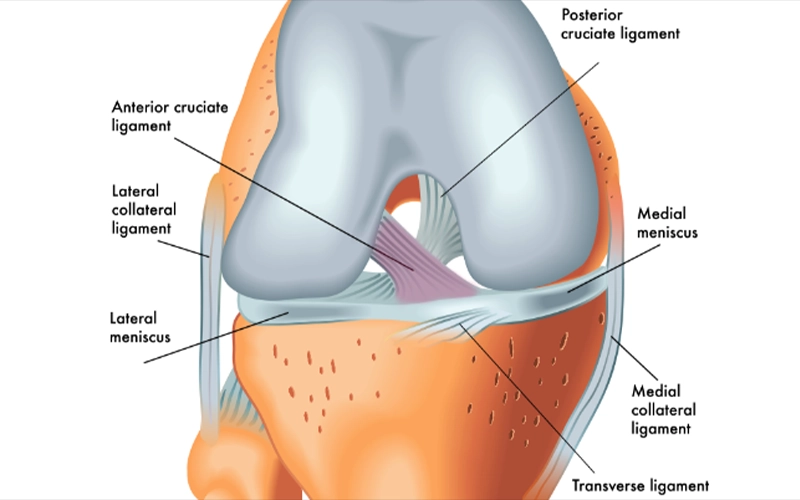

منیسکهای زانو از نظر خونرسانی به سه ناحیه اصلی تقسیم میشوند: ناحیه قرمز (Red Zone)، قرمز–سفید (Red-White Zone) و سفید (White Zone) که از حاشیه به سمت مرکز منیسک قرار دارند.

بهجز بخش محیطی منیسکها، سایر قسمتها فاقد عروق خونی هستند و تغذیه آنها از طریق انتشار مواد غذایی از مایع مفصلی انجام میشود. حدود ۱۰ تا ۳۰ درصد از حاشیه خارجی منیسک خارجی و ۱۰ تا ۲۵ درصد از حاشیه منیسک داخلی دارای عروق خونی هستند.

اعصاب منیسکها مسیر عروق را دنبال میکنند و بیشترین تراکم عصبی در نواحی شاخ قدامی و شاخ خلفی منیسکها دیده میشود که نقش مهمی در حس عمقی و درد زانو دارند.

ویژگیهای منیسک داخلی زانو

منیسک داخلی زانو ساختاری به شکل حرف C باز دارد و شعاع انحنای آن از منیسک خارجی بیشتر است. ...